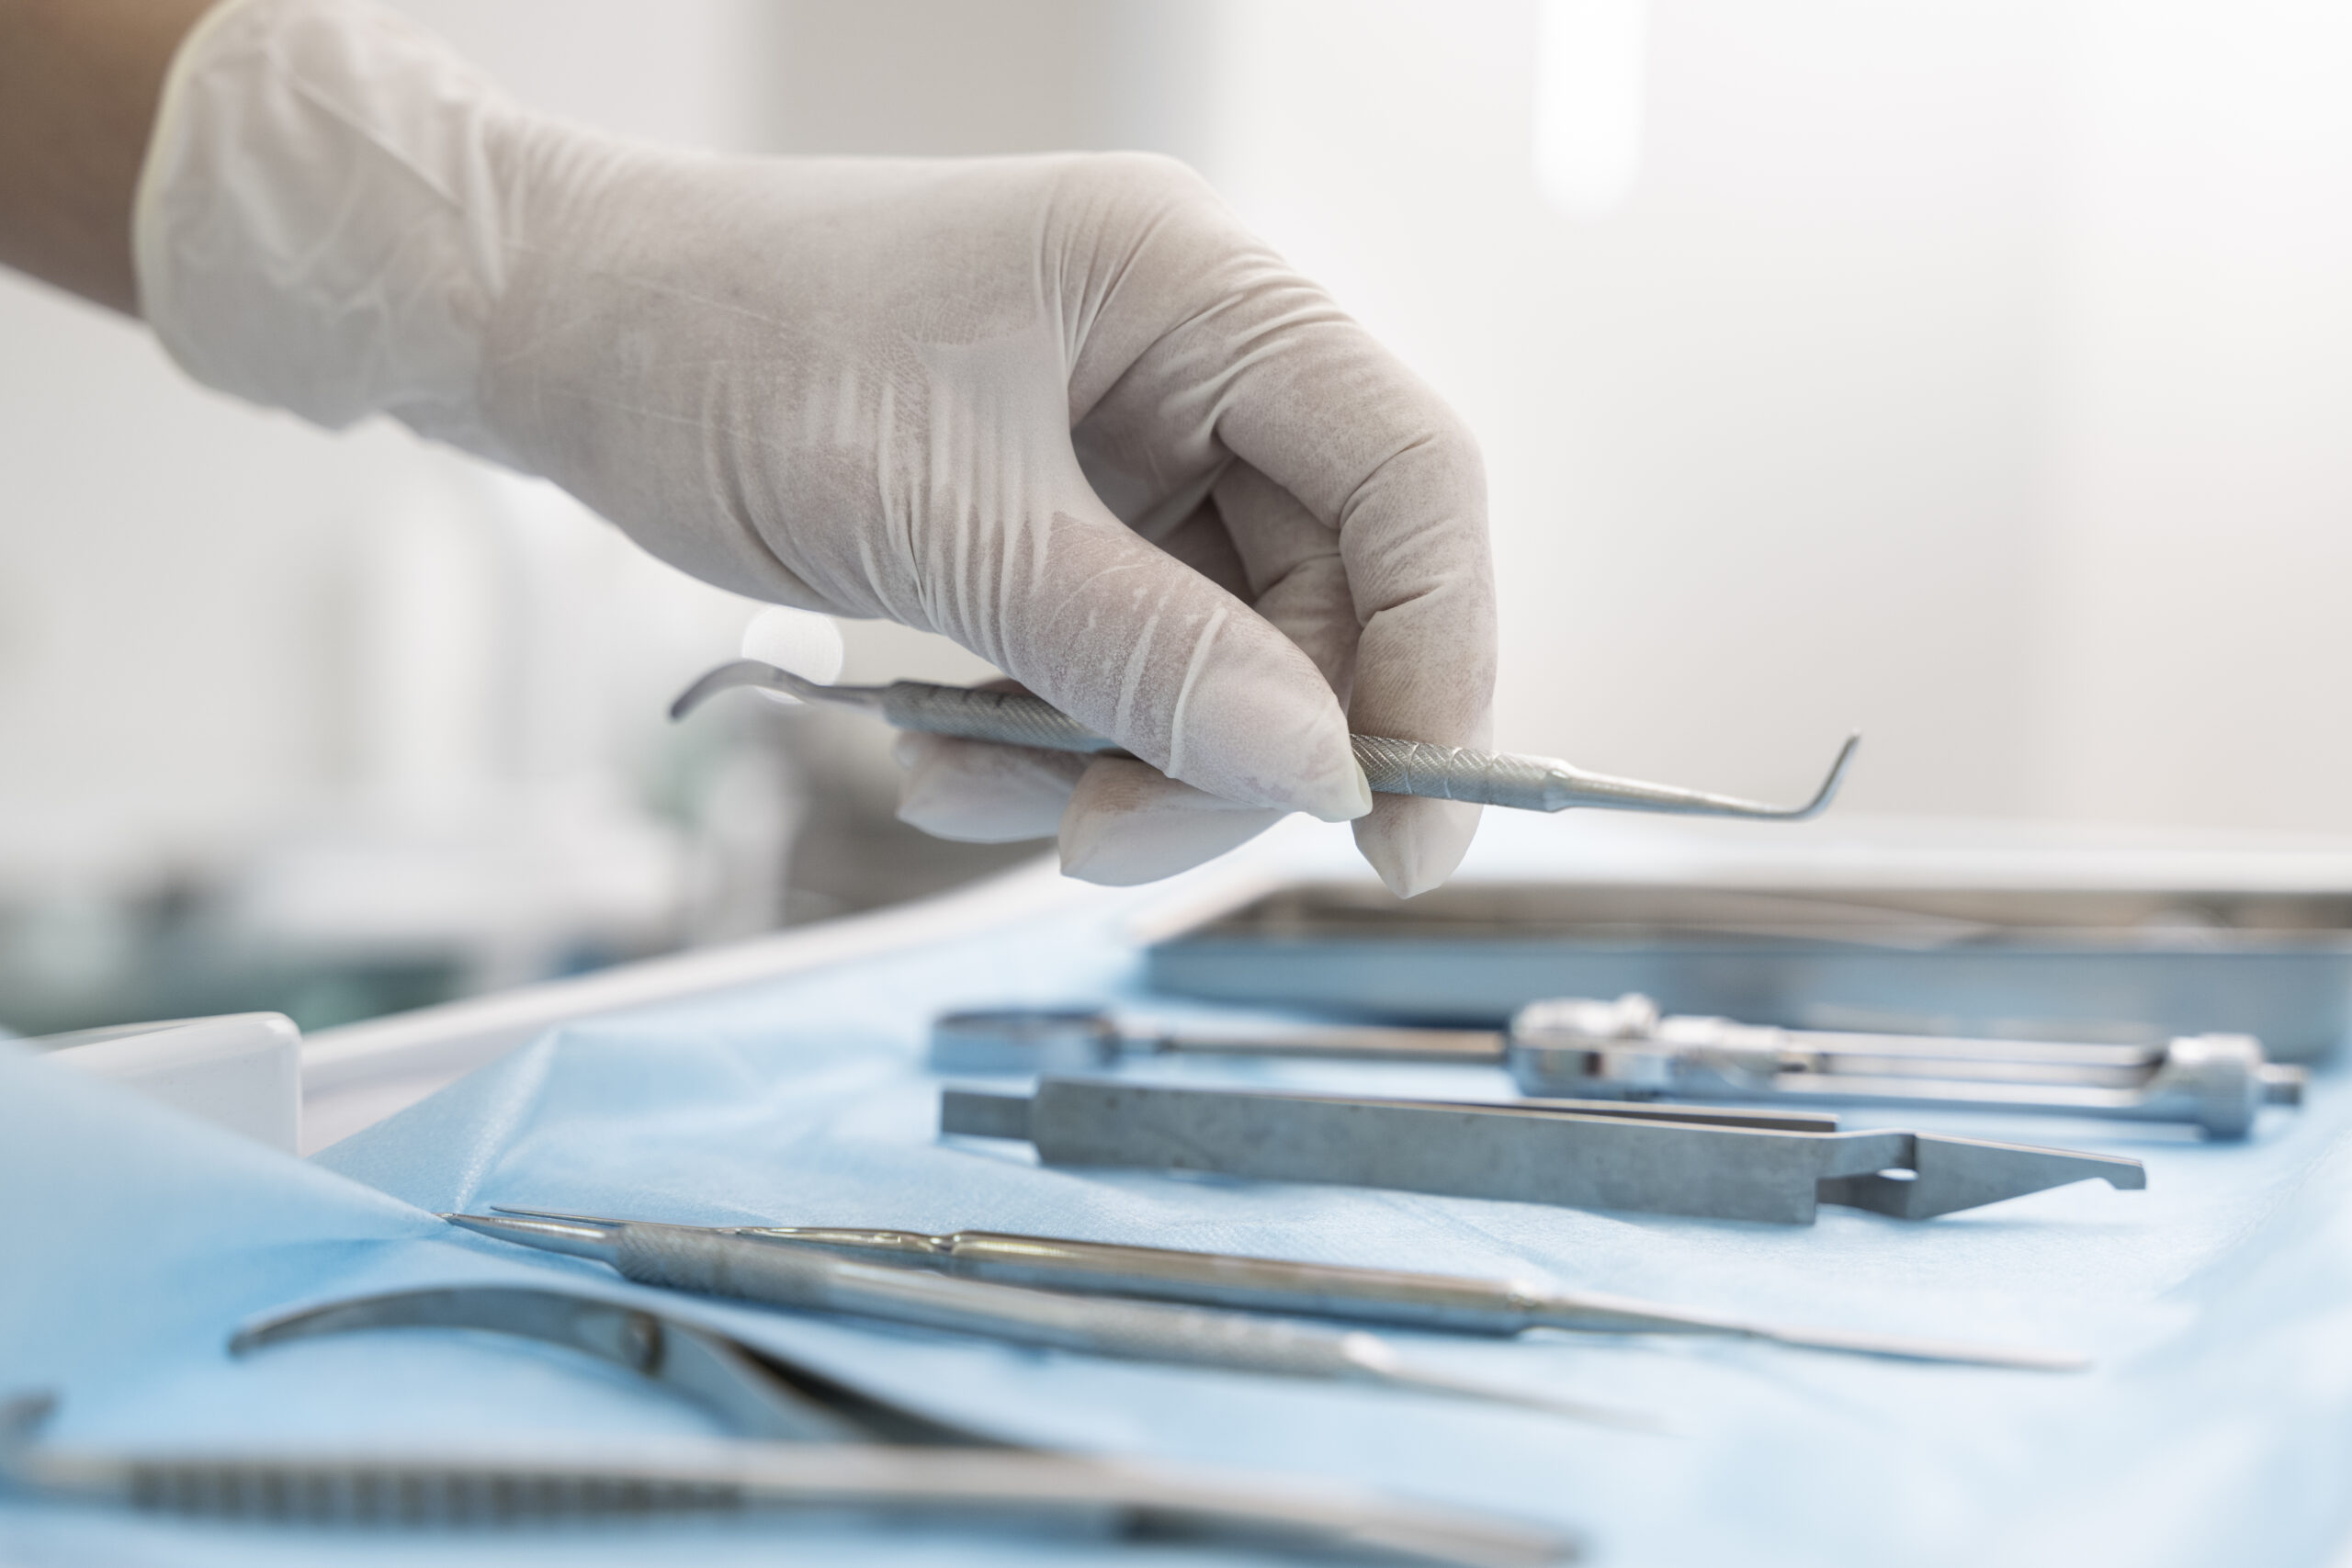

Oralchirurgie

Unsere Oralchirurgie vereint moderne chirurgische Verfahren mit zahnmedizinischer Expertise – für sichere, schonende und präzise Behandlungen